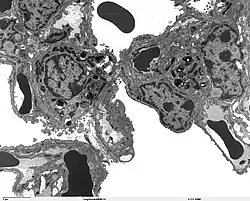

The protein encoded by this gene (SP-A2) is primarily synthesized in lung alveolar type II cells, as part of a complex of lipids and proteins known as pulmonary surfactant. The function of this complex is to reduce surface tension in the alveolus and prevent collapse during expiration. The protein component of surfactant helps in the modulation of the innate immune response, and inflammatory processes.[7]

SFTPA2 expression

The lung is the main site of SFTPA2 synthesis, but SFTPA2 mRNA expression has also been detected in the trachea, prostate, pancreas, thymus, colon, eye, salivary gland and other tissues. While the majority of these tissues express both SFTPA2 and SFTPA1 transcripts, only SFTPA2 expression was found in the trachea and prostate.[15] Using specific monoclonal antibodies for Surfactant protein A, the protein can be detected in lung alveolar type II pneumocytes, Club cells, and alveolar macrophages, but no extrapulmonary SP-A immunoreactivity was observed.[15]